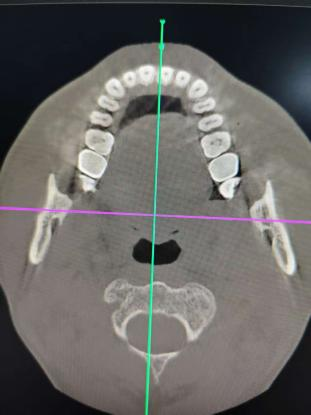

口腔CT,也就是口腔锥形束CT(CBCT),是目前国际最先进的口腔科专用检查设备,是利用锥束投影,借助X线扫描检测部位,然后将所得到的数据在计算机中重组、成像,可以直接观察检测者反应颌面组织三维空间结构,应用范围较广,牙周病科、口腔颌面外科学、种植牙、正畸学等科室都需要借助这项检查来为病情诊断、治疗计划以及恢复情况来提供客观依据。

具有精度高、辐射小、费用低、分辨率高、定位准确、图像清晰、避免重叠等特点,为口腔疾病的诊疗提供了精准的影像保障和技术支持。

1. 扫描方式采用锥形束360o容积扫描方式,采集的信息量更多, 扫描范围更大,扫描间更短。

2.辐射剂量更低,对于获取相近的信息量,辐射剂量仅为普通CT的几十分之一。

3.影像后期处理功能强大,彩色三维重建从上下、左右、前后各个方向任意旋转,可以任意层厚、 任意层距、任意切面,多方位、多角度的观察病变。

4.适用范围更广、诊断更加准确。牙齿种植术前骨量及密度分析,埋伏牙的准确定位,复杂的根尖周病变诊断,阻生齿拔除方案的详细制定,颌骨囊肿范围的确定, 颞下颌关节骨质的检查等。